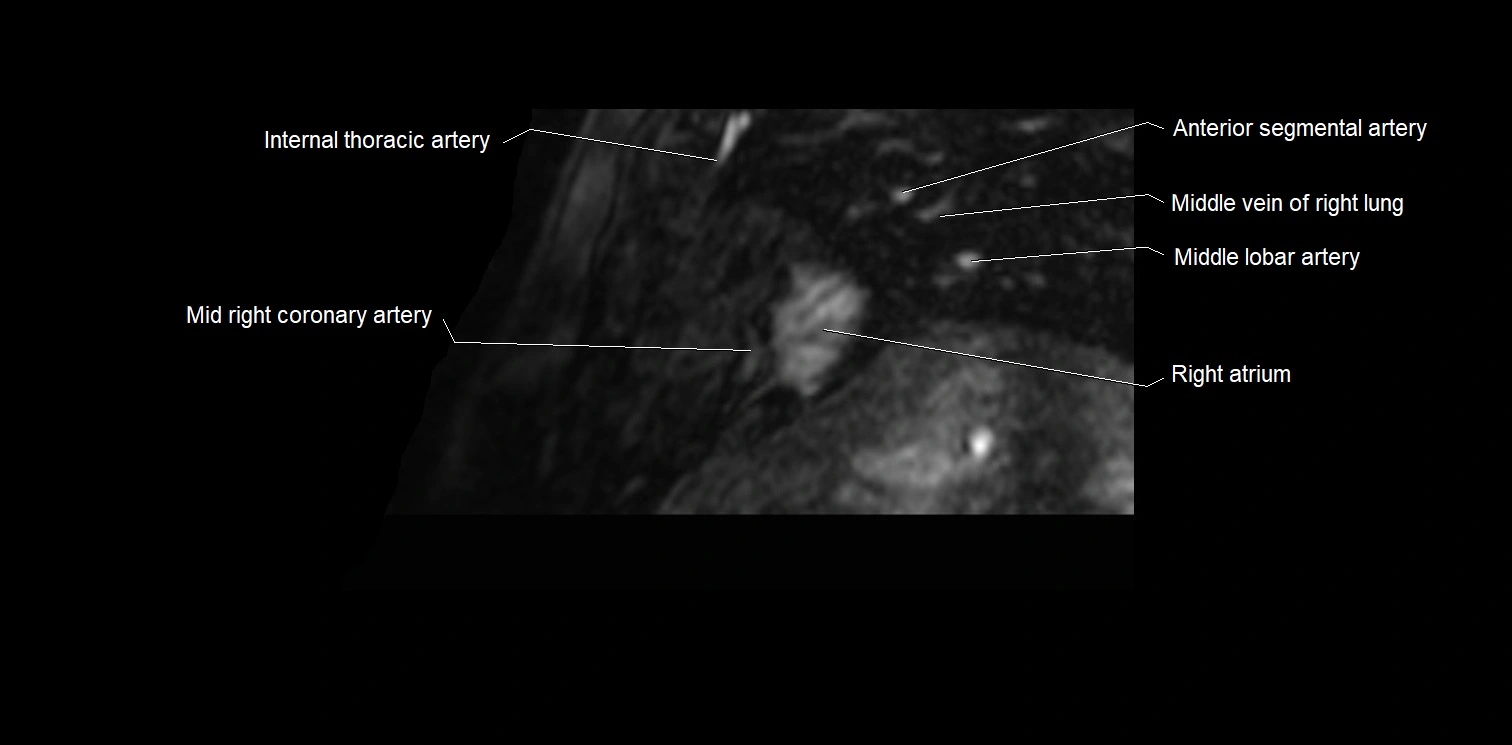

CT images